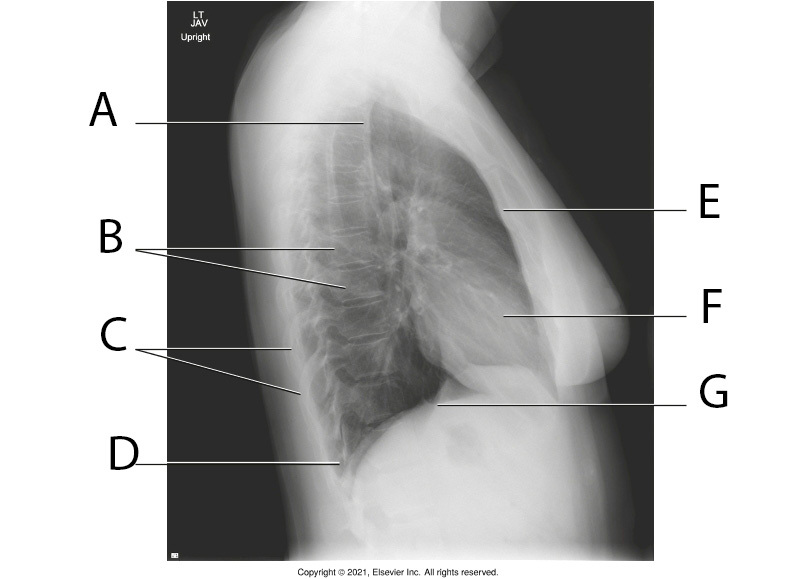

Q

A

Apicies

11

B

Thoracic Vertabrae

12

C

Posterior Ribs

13

D

Costrophrenic Angle

14

E

Body of Sternum

15

F

Heart

16

G